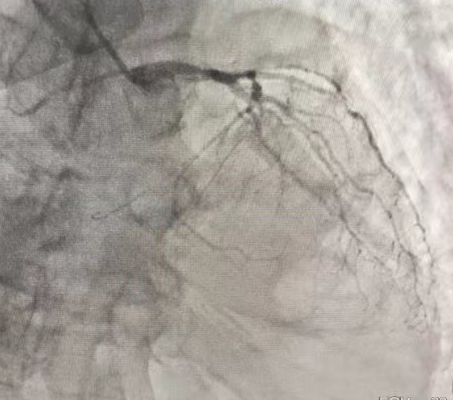

冠脉造影结果显示,患者面临的是极其危险的冠脉三支病变,远端血流受到极大影响,左前降支血管中断闭塞,左回旋支75%-90%的狭窄,右冠状动脉99%的狭窄。蒋小菊在查看造影结果后明确指出,要尽快开通血管。在呼吸机的辅助支持下,心血管内科团队成功为患者闭塞的血管破开道路,顺利完成了救治。